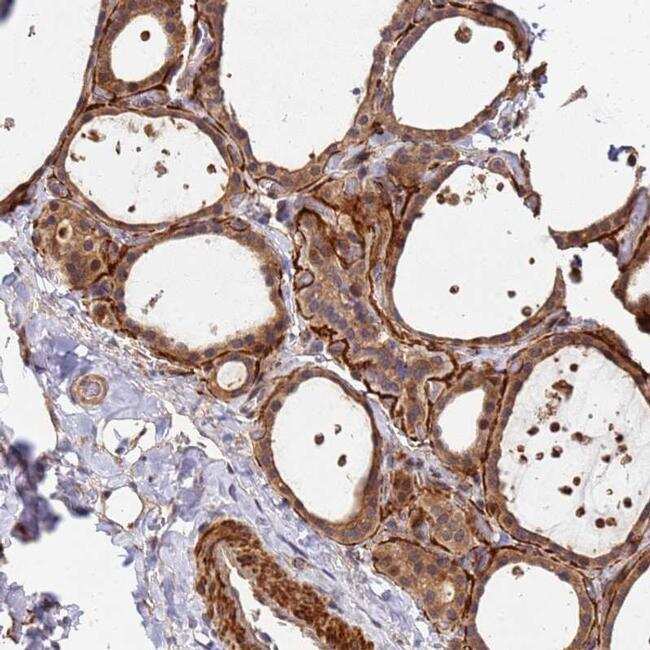

Supportive validation

- Submitted by

- Invitrogen Antibodies (provider)

- Main image

- Experimental details

- Immunohistochemical analysis of DUS4L in human thyroid gland using DUS4L Polyclonal Antibody (Product # PA5-60671) shows moderate cytoplasmic positivity in glandular cells.